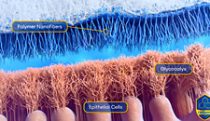

antibody and villi

Work -